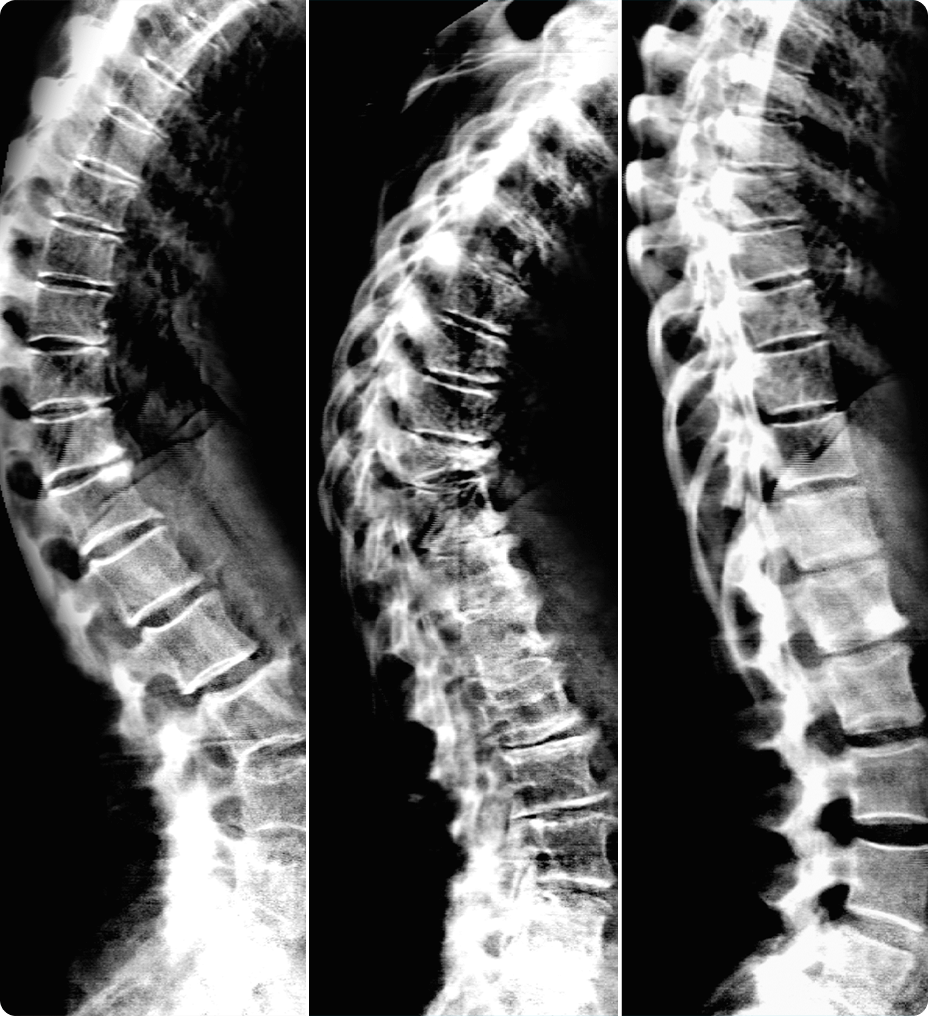

Score osseux trabéculaire (TBS) intégré2 L’application Score osseux trabéculaire (TBS) utilise une acquisition DXA du rachis AP pour évaluer la micro-architecture des os et fournir un score TBS. Cette application en option permet d’avoir une meilleure compréhension de la qualité des os (en plus de la quantité d’os grâce à l’analyse de la DMO), afin d’offrir des informations supplémentaires sur la santé osseuse du patient. Combiné à la DMO et au FRAX, le TBS peut être particulièrement utile pour évaluer les patients dont la DMO est à la limite de l’ostéoporose. Image à droite : Compte rendu sur la santé osseuse